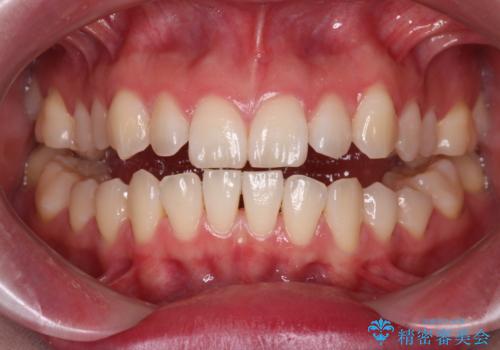

【ワイヤー矯正】がたつきを治したい